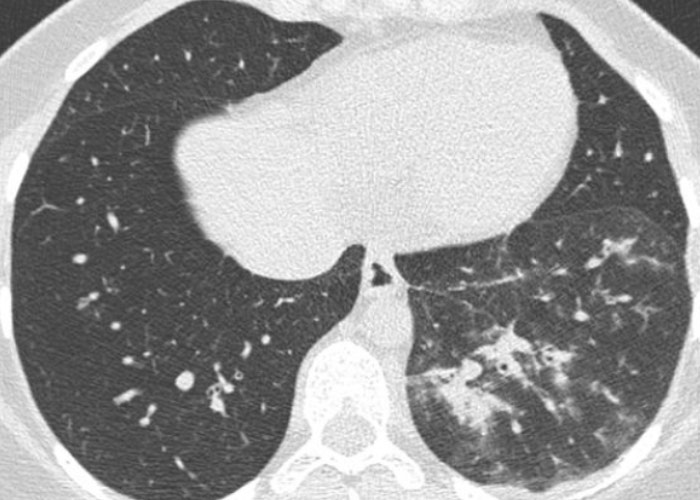

| pneumonie interstitielle | plages de verre dépoli, réticulations (viral, mycoplasma, chlamydia, pneumocystose) |  |